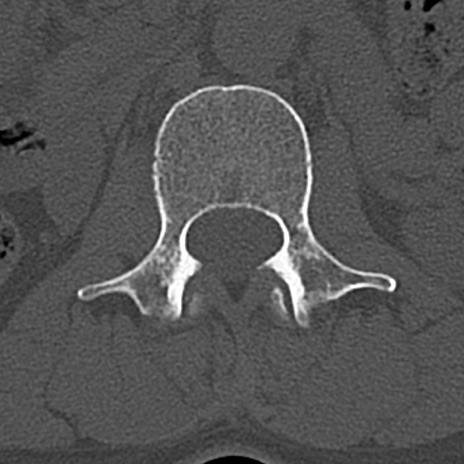

【整形】TIPS症例4 腰椎CT(横断像)

腰椎CT

横断像と矢状断像